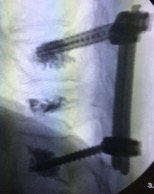

Рис. 2. Окончательная фиксация повреждённого сегмента позвоночника без существенной коррекции и реконструкции

(Стабильный компрессионный перелом позвонка. Альтернатива консервативным методам лечения с длительным периодом корсетирования и реабилитации).